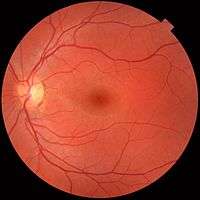

The interior of the posterior half of the left eyeball.

The interior of the posterior half of the left eyeball. A fundus photograph showing the macula as a spot to the left. The optic disc is the area on the right where blood vessels converge. The grey, more diffuse spot in the centre is a shadow artifact.

A fundus photograph showing the macula as a spot to the left. The optic disc is the area on the right where blood vessels converge. The grey, more diffuse spot in the centre is a shadow artifact.